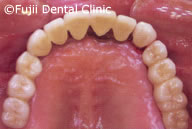

| 術後パノラマ写真および口腔内写真 |

ヘビースモーカーであったために、禁煙してもらい、歯のクリーニングやブラッシング指導後、およそ2年間かけて左上犬歯と左下第一小臼歯以外すべての歯を抜歯し、インプラントの埋入手術を行いました。左右上顎臼歯部はサイナスリフトなどを併用し、インプラントによる咬合の再構築を試みました。